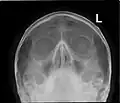

Paranasal sinuses seen in a frontal view

Paranasal sinuses are a group of four paired air-filled spaces that surround the nasal cavity.[1] The maxillary sinuses are located under the eyes; the frontal sinuses are above the eyes; the ethmoidal sinuses are between the eyes, and the sphenoidal sinuses are behind the eyes. The sinuses are named for the facial bones and sphenoid bone in which they are located. The role of the sinuses is still debated.